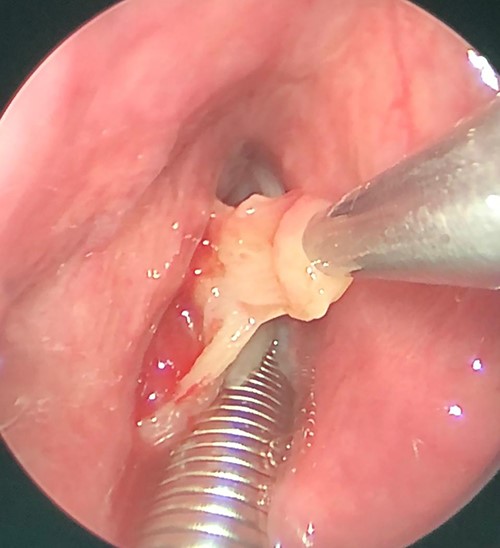

Patient was booked for direct laryngobronchoscopy with left false vocal cord mass excisional biopsy using Co2 laser. Examination under general anesthesia showed the mass extending from the left false vocal cord to the left ventricle (Figs 3 and 4). It measured 2 × 0.5 × 1 cm. The subglottic area was patent with no masses seen (Fig. 5). The mass was excised completely using Co2 laser aiding in patent airway (Fig. 6). Specimen was sent for histopathology.

Intraoperative picture, showing left sided mass originated from left false vocal fold.